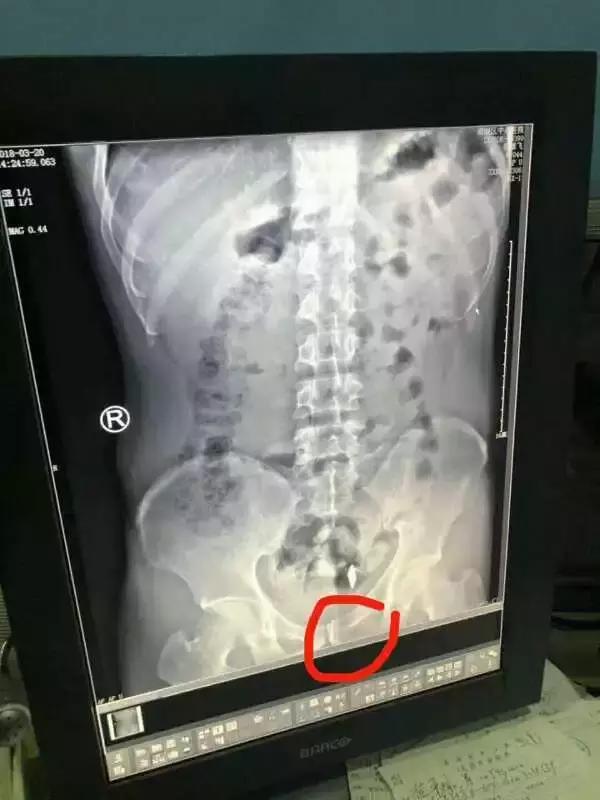

阮某自然也遵循着这个*规则潜**,在前后4次被建设派出所抓获的经历中,每次他的肚子里总是有异物,办案民警每次抓获后只能无奈将其取保候审。“第一次吞是在2008年吧,跟着别人学的,拿胶带纸在刀片外面裹几层,以防割破身体内脏。”被刑事拘留后的阮某说,“因为这些物品会在一段时间内自然排出体外,但也有钢针类金属因挂在肠壁上长时间难以排出。”在不确定异物是否被排出体外的情况下,他每隔几天就要吞入一枚刀片或者钢针,以逃避法律制裁。

3月15日,建设派出所民警在阮某的住所将其抓获,并马上将他带到第二医院检查,在X光的照射下,藏于阮某体内胃部和肠道内的2枚单面刀片和1枚钢针非常醒目。通过胃镜手术,一枚刀片被取出,后又通过服用粗纤维蔬菜及石蜡油润肠,另外两样异物也终于从阮某体内被排了出来。3枚异物的长度都大约在4厘米。3月21日,阮某被成功送押到嘉兴市看守所,经审讯,他交代了为满足毒资实施扒窃的犯罪事实。